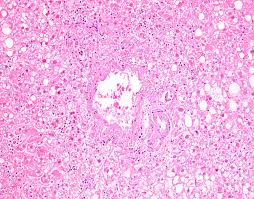

Esophagitis caused by herpes simplex virus (hsv) is frequently documented during periods of immunosuppression in patients infected with human immunodeficiency virus (hiv). Lymphocytic esophagitis is characterized by high numbers of intraepithelial lymphocytes (iels) gathered mainly around peripapillary fields and by none (n = 12) to occasional (n = 8) cd15+ intraepithelial granulocytes. The histology of herpes infections is very distinctive. The acute inflammation can be caused by infections, ingestion of irritative chemicals, drugs such as nsaids, chemotherapy, and radiation. His immunological work up showed normal level of immunoglobulins and his white blood cells subpopulations were normal. We reviewed 16 cases of hsv esophagitis diagnosed from january 1982 to march 2016. The low power pattern of a typical lesion. Hsv esophagitis is usually identified in patients with aids or other significant immunosuppressive conditions, although cases in healthy adults also occur.

Hsv esophagitis is usually identified in patients with aids or other significant immunosuppressive conditions, although cases in healthy adults also occur. He had no history of recurrent infections or history of sick contacts. This condition can also occur as a primary infection in individuals taking immunosuppressive drugs and it is therefore considered as an opportunistic disease [ 1 Forms of esophagitis have been recognized for millennia; His immunological work up showed normal level of immunoglobulins and his white blood cells subpopulations were normal. His hsv serology was positive. We reviewed 16 cases of hsv esophagitis diagnosed from january 1982 to march 2016. Acute esophagitis is manifested here by increased neutrophils in the submucosa as well as neutrophils infiltrating into the squamous mucosa at the right. We reviewed 16 cases of hsv esophagitis diagnosed from january 1982 to march 2016. The aim of this retrospective study is to identify comorbid and predisposing conditions and sequelae of hsv esophagitis in immunocompetent children. Elongated papillae >2/3 of the thickness of the mucosa #2 most common cause of infectious esophagitis after candida self limited in healthy patients; Herpes esophagitis is caused by hsv type 1.

The aim of this retrospective study is to identify comorbid and predisposing conditions and sequelae of hsv esophagitis in immunocompetent children. #2 most common cause of infectious esophagitis after candida self limited in healthy patients; The differential diagnosis in a patient with a swallowing disorder or other problem with food intake includes both local and systemic problems. Concomitant herpetic and candidal esophagitis is a very rare disease that had not been reported in uremic patients. We reviewed 16 cases of hsv esophagitis diagnosed from january 1982 to march 2016. All three of the following are required for the diagnosis of gerd; The esophagus is a muscular tube that carries food and drink from your mouth to your stomach. Acute esophagitis is manifested here by increased neutrophils in the submucosa as well as neutrophils infiltrating into the squamous mucosa at the right.